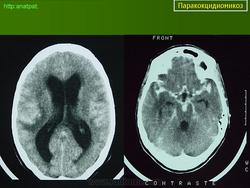

ГМ. Паракокцидиомикоз. +

Паракокцидиомикоз.

Множественные "узловые образования" имитирующие метастазы.